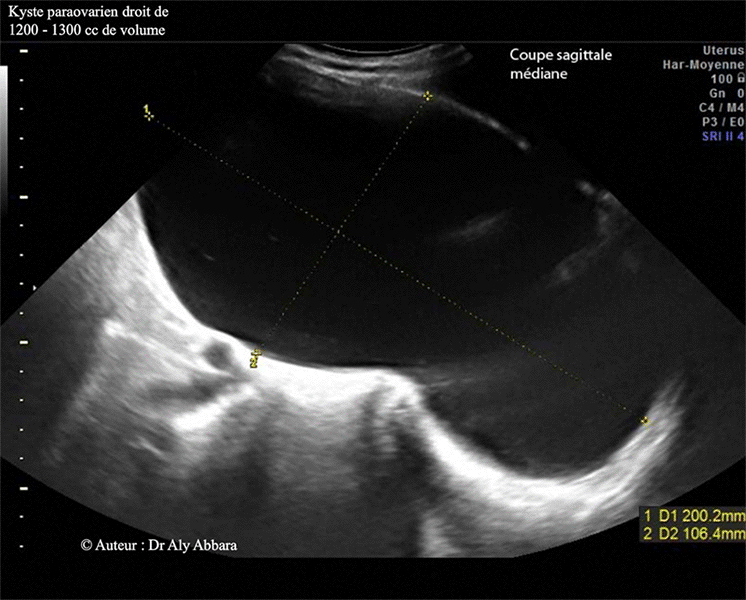

Il s'agit d'un kyste uniloculaire de 200 x 110 x 106 mm de dimensions (soit environ 1230 cm3 de volume), à paroi fine, sans végétations endophytiques et sans épanchement péritonéal.

Kyste para-ovarien droit (aspect échographie et macroscopique).